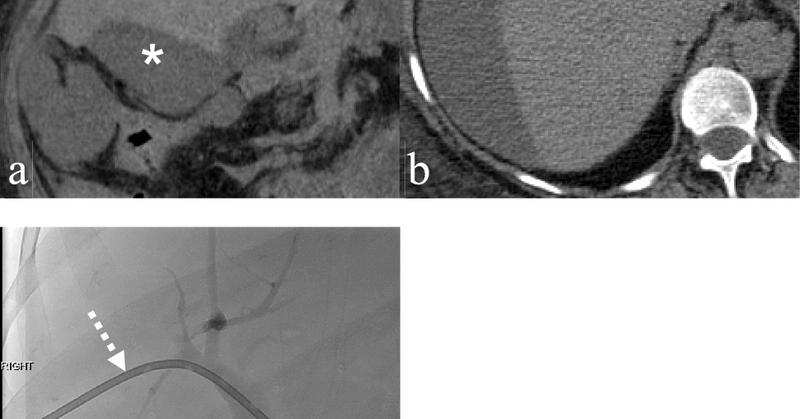

Challenge yourself with a case brought to you by Malak Itani, MD @ItaniMalak from @WashUMedMIR: 70M with RUQ pain x 1 week with nodular thickening of the GB wall, superimposed on changes of cholecystitis on initial CT, s/p cholecystostomy tube on MR.

Axial and coronal contrast enhanced CT images demonstrating: Multiple discrete and confluent areas of cystic change within the gallbladder wall which is markedly thickened, continuous enhancement of the mucosa and serosa Answer: Xanthogranulomatous cholecystitis

•Pre and post-contrast T1 fat saturation images: predominately T1 hypointense mass with areas of intrinsic enhancement. Answer: Intraductal papillary neoplasm of the bile duct (IPNB)

Axial diffusion weighted imaging: mass and filling defects demonstrate hyperintense signal on high B value diffusion imaging •MRCP and axial T2 fat saturation: diffuse intrahepatic biliary duct dilation; axial T2 fat saturation images confirm HASTE findings.

•Axial and coronal T2WI (HASTE sequences): An ~9cm hepatic mass with heterogenous, but predominately hyperintense signal, on T2WI. Associated intrahepatic biliary duct dilation with multiple curvilinear hypointense striations/filling defects.